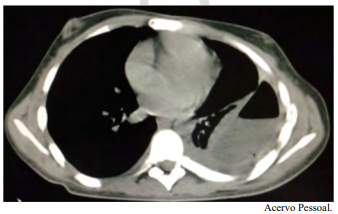

Espera-se, na análise do líquido pleural desse paciente, um exsudato com predomínio linfocítico e ADA elevado.

O paciente tem indicação de pleuroscopia para descorticação pulmonar e biópsia de pleura.

O paciente tem indicação de ressecção de tumor de mediastino por VATS.

Teratoma, timoma e schwannoma são diagnósticos diferenciais dos tumores de mediastino anterior.